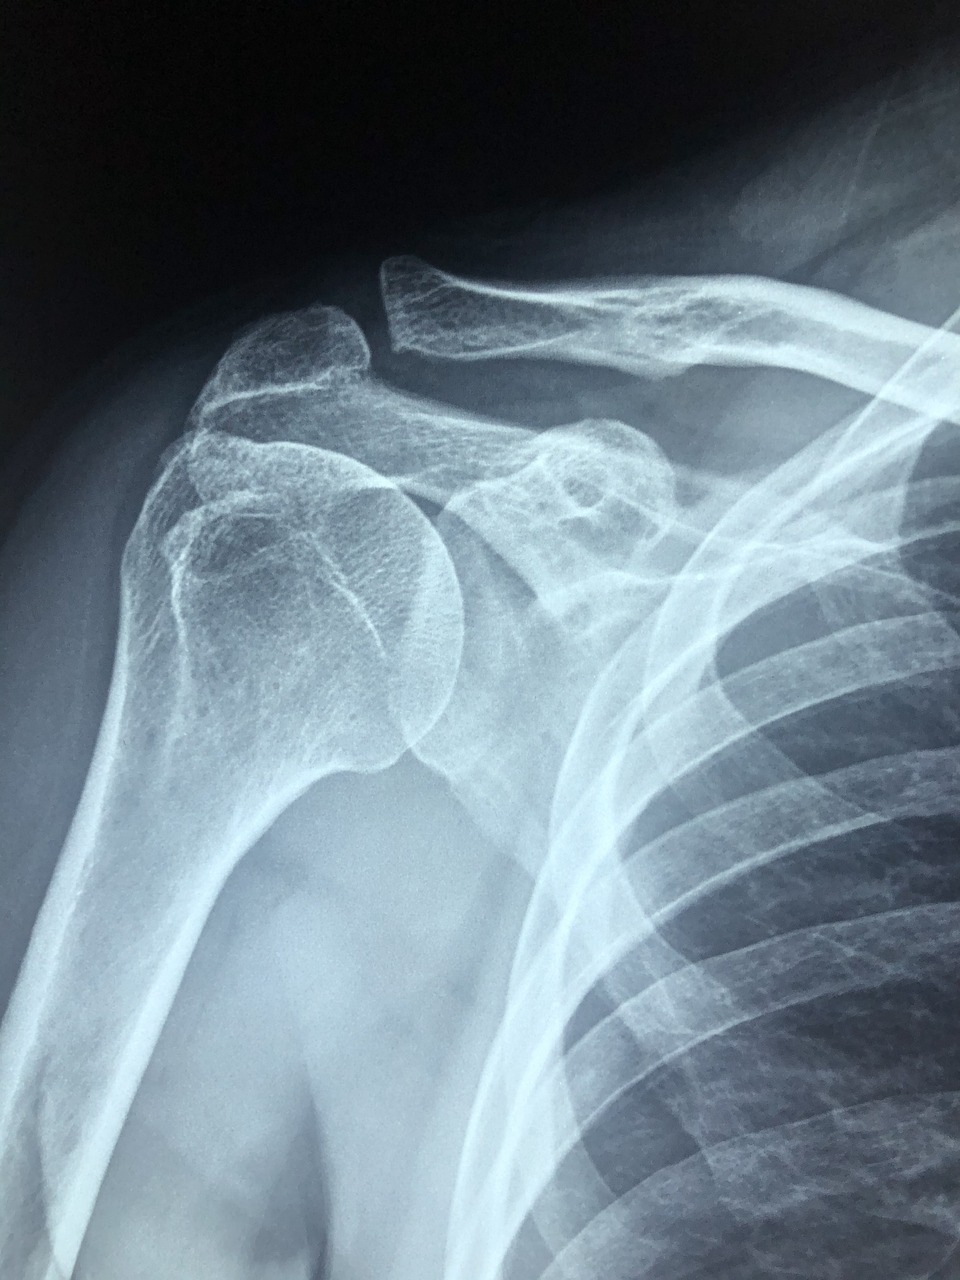

✅ 회전근개 파열

회전근개는 어깨 관절을 감싸고 있는 4개의 근육과 힘줄을 말하는데요, 주로 팔을 자주 드는 직업(예: 미용사, 주방장, 간호사 등)에서 많이 발생해요.

- ● 어깨를 올리거나 돌릴 때 극심한 통증

- ● 팔을 누가 들어줘야 할 만큼 힘이 빠짐

비수술 치료로는 체외충격파, 주사치료, 운동치료 등이 있으며, 조기 발견 시 6주~12주면 통증이 상당히 개선될 수 있습니다.